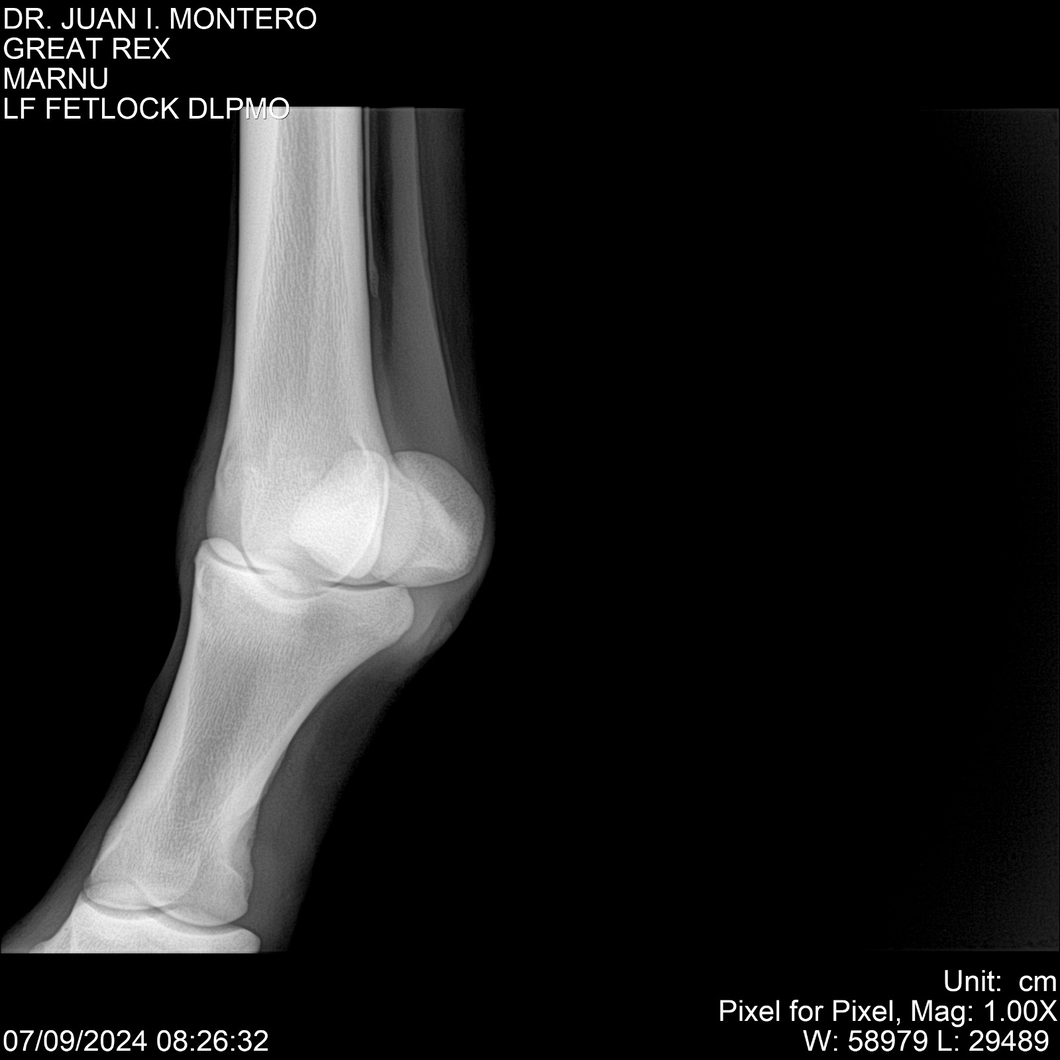

LOTE 4, GREAT REX Lote Anterior Volver al remate Lote Siguiente Ficha Contacto Montevideo - Ficha del Lote Identificador: #282518 Categoría: Yeguarizos Montevideo - 66 Visualizaciones ClicData Contacto Empresa: Abelenda N. R., Walter Hugo Nombre*: Teléfono* : E-mail* : Mensaje Enviar Registrese gratis Este contenido Exclusivo está disponible sólo para usuarios registrados Ingresar